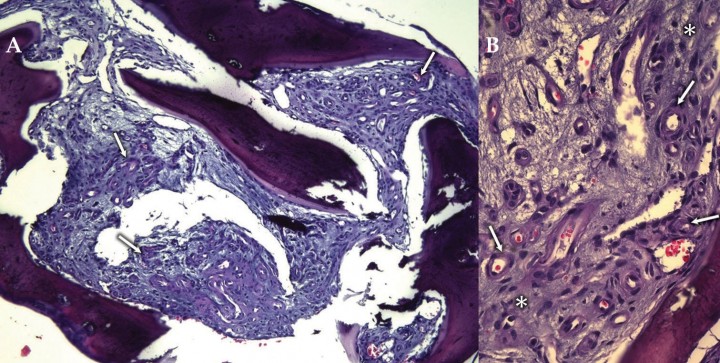

Cinco días después se realizó una hemilaminectomía T5-T7 izquierda para la descompresión del cordón medular. La lámina y pedículos de T6 manifestaban una apariencia rugosa/granulada de consistencia normal. Tras la hemilaminectomía se observó que el tejido óseo invadía el canal vertebral donde no había grasa epidural y el cordón medular aparecía deformado. Se procedió a la retirada del tejido mediante fresado y raspado con gubias y cureta y se procesó una muestra para su estudio histopatológico. Éste reveló la existencia de tejido óseo trabecular con abundante tejido conjuntivo laxo entre las trabéculas que mostraban una escasa cantidad de células hematopoyéticas. Entre las fibras de colágeno se apreció una proliferación de células endoteliales organizadas formando abundantes estructuras vasculares de conformación tortuosa, ramificada o compacta (Fig. 4). Teniendo en cuenta los hallazgos anatomopatológicos el diagnóstico definitivo fue el de angiomatosis vertebral.

<p>(<strong>A</strong>) Imagen microscópica en la que se aprecia tejido óseo trabecular con escasa población hematopoyética que ha sido sustituida por tejido conjuntivo laxo que contiene estructuras vasculares de diferente calibre (flechas). (<strong>B</strong>) Imagen microscópica en la que se aprecian capilares con endotelio reactivo (morfología fusiforme, núcleo hipercromático y cromatina densa) (flechas) rodeados de fibras musculares lisas en un estroma conjuntivo basófilo (asterisco). Hematoxilina-Eosina (<strong>A</strong> y <strong>B</strong>) . Aumentos: 20x (<strong>A</strong>) y 200x (<strong>B</strong>).</p>

(A) Imagen microscópica en la que se aprecia tejido óseo trabecular con escasa población hematopoyética que ha sido sustituida por tejido conjuntivo laxo que contiene estructuras vasculares de diferente calibre (flechas). (B) Imagen microscópica en la que se aprecian capilares con endotelio reactivo (morfología fusiforme, núcleo hipercromático y cromatina densa) (flechas) rodeados de fibras musculares lisas en un estroma conjuntivo basófilo (asterisco). Hematoxilina-Eosina (A y B) . Aumentos: 20x (A) y 200x (B).